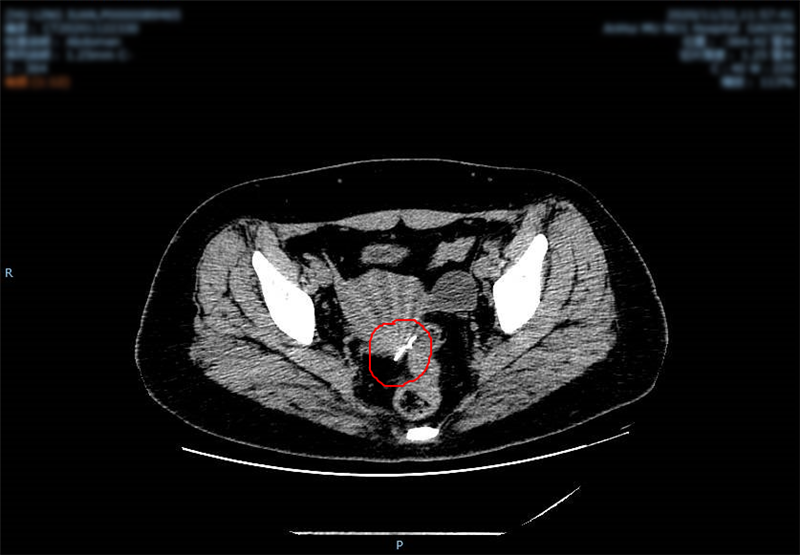

朱女士今年34岁,据她回忆,自己儿时曾经误吞下一根针,一直没有明显不适,但最近备孕做MRI(核磁共振成像)检查时,因体内有金属异物无法继续进行,后改为CT检查,发现针已经戳破直肠,游走到盆腔,如怀孕很可能会引起子宫损伤甚至伤及婴儿,非常危险。

据李永翔介绍,由于针在体内容易游走,定位困难,决定为其采用腔镜手术联合腔镜下超声内镜技术,“治疗”和“观察”同步进行,精准定位,为取针提供保障。经过充分的术前准备,一根长达3.5cm的缝衣针顺利从朱女士的体内取出,针已经出现生锈和腐蚀。整个过程仅30分钟,出血少,创伤小。